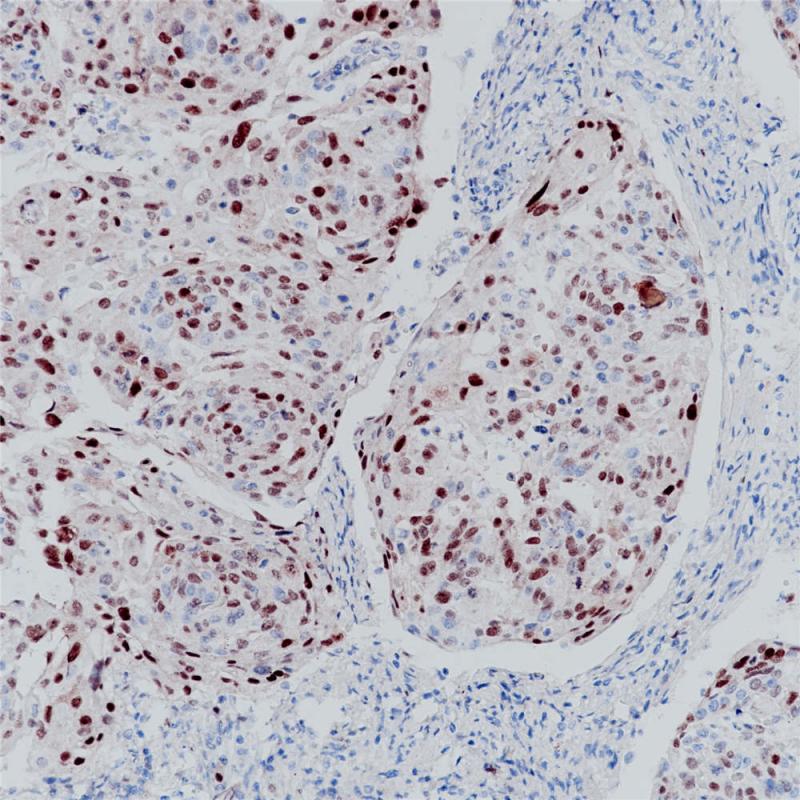

p21 重组兔单克隆抗体

p21是由位于6号染色体(6 p21.2)的CDKN1A基因编码的蛋白,也被称为细胞周期依赖性激酶抑制剂。p21与CDK2/CDK4结合的同时会抑制他们的活性,从而在G1期起调节细胞周期进程的作用。p21在所有成人组织中表达,在肿瘤组织中也有广泛地表达,例如胃癌、非小细胞肺癌、甲状腺癌。p21表达通常与预后良好相关。

阳性对照

宫颈癌

亚细胞定位

细胞核